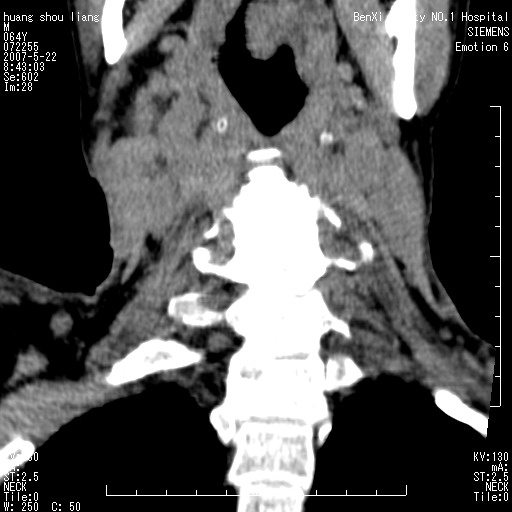

男性,64岁。颈部包块8年。最近增大。

对不起大家,可能是片子发太多有点乱,正常腮腺在下颌角的外侧,颌下腺在下颌体的中部内侧,本例在下颌角内侧偏下,和腺体一点关系都没有,从vrt和mpr上可以很明显看出来,再者肿块是好多粘连在一块的,大家在仔细看看,左侧可能也是吧,我还是考虑为肿大的淋巴结融合在一块,但性质??????

右侧腮腺下部均匀软组织密度肿块,外形不规则,与周围组织分界清晰,考虑右侧腮腺混合瘤或多形性腺瘤。

大家好,病理结果出来了,如大家所说,颌下腺混合瘤。

唉,解剖没学好吧,我诊断错了,不过还是有些不理解回去我在多看看书,谢谢大家的参与,以后我还会奉献好的病例。